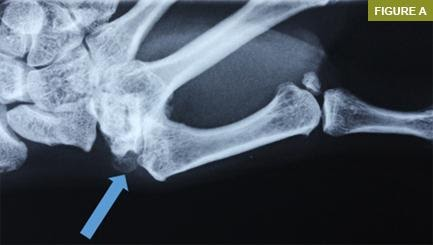

BAŞPARMAĞIN AĞRILI DURUMLARI

1. Başparmak Artriti (Osteoartrit)

Başparmak eklemindeki kıkırdağın aşınması sonucu meydana gelen osteoartrit, ağrıya ve hareket kısıtlılığına yol açabilir. Özellikle yaş ilerledikçe, başparmak eklemindeki kıkırdak hasarı artar. Bu durum, başparmağınızda şişlik, sertlik ve ağrı hissine neden olabilir.

3. Başparmak Burkulması ve Yaralanmaları

Başparmakta travma, burkulma veya zorlama, akut ağrıya neden olabilir. Spor yaparken veya herhangi bir kazada başparmağınızın aniden zorlanması, dokularda hasara yol açabilir. Başparmak burkulması, şişlik ve ağrı ile kendini gösterir.

Başparmak elin %50’sini temsil eder. Parmak eksikliği ile elin fonksiyonel kullanımı mümkün iken, başparmağın fonksiyonunun kaybedilmesi, elin birçok dinamik fonksiyonunun ve çimdik kavramanın kaybına yol açacaktır.

Başparmağın yaygın ağrılı durumları şunları içerir:

- tetik başparmağı

- başparmağın sesamoiditi

- başparmak eklemlerindeki bağ yaralanmaları (interfalangeal eklem dahil)

- metakarpal falanks eklemi

- karpometakarpal falanks eklemleri